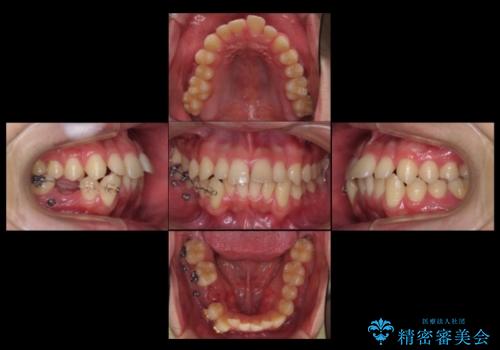

- 前歯の並びをきにして来院。

歯を抜かずに、やすりがけすることでスペースを獲得し、前歯をしっかり下げました。

また、インビザラインに先駆けて、右下はワイヤーによる部分矯正を行い、犬歯をしっかり後ろに下げました。

下げる時に、矯正用ミニスクリューを使用しています。

右下に乳歯が残っていましたが、後に続く永久歯がありませんでした。

乳歯も根が吸収しており長くは持たない状況でしたので、まず乳歯を抜歯し、他の歯を矯正治療で歯を並べてからインプラントで補綴しました。

先にインプラントをしてしまうと、矯正治療で周りの歯を動かす事ができなくなってしまいます。

矯正治療→インプラントの順で行います。